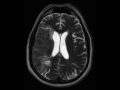

Laminar Necrosis

64-year-old male with a history of a large right middle cerebral artery infarct. The fluid sensitive images demonstrate residual edema and loss of gray-white matter differentiation within the right MCA territory. There is also residual effacement of the overlying cerebral cortical sulci with very slight effacement of the body and atrium of the right lateral ventricle. The susceptibility weighted images demonstrate curvilinear regions of signal loss along the cortical gray matter of the right frontoparietotemporal regions as well as of the insula. Findings are compatible with cortical laminar necrosis in the setting of recent infarct. Cortical laminar necrosis is secondary to selective vulnerability or watershed cortical layers. Neurons and glial cells are equally affected. Causes include hypoperfusion, hypoxia, status epileptics, hypoglycemia and severe anemia.